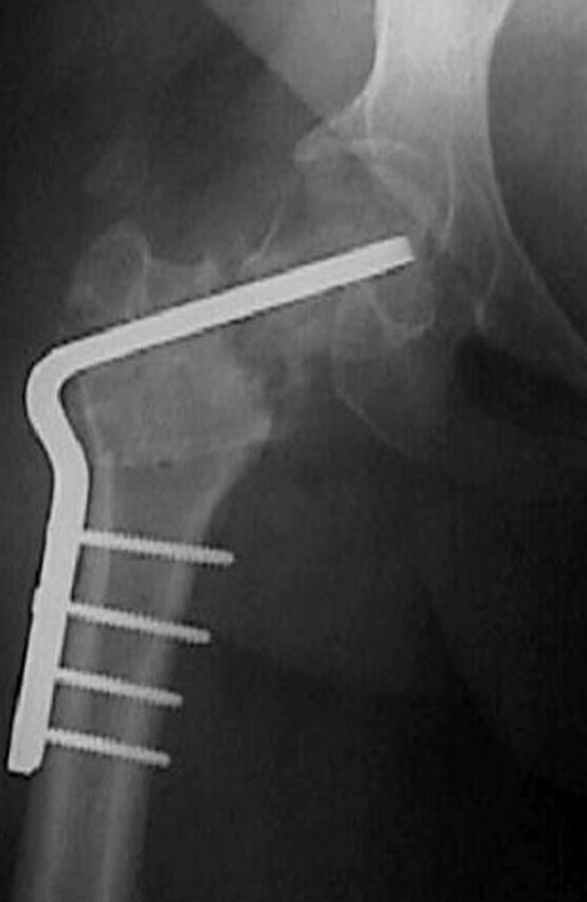

Несколько снимков из моей коллекции, чтобы разьяснить, почему мы до сих пор делаем различные варианты остеотомии.

На рисунке N1 предоперационный план лечения ложного сустава шейки бедра- линия ложного сустава, угол и направление введения импланта, клиновидная остеотомия в градусах и миллиметрах, второй снимок после коррекции, расчет, на сколько удлиняется конечность и размеры импланта;

N3 рисунок окончательный снимок, после операции моя рентгенограмма должен выглядеть примерно как эта картина. На N4 снимке клин перед удалением; N5 послеоперации 3 нед.; N6 окончательная рентгенограмма.

варус при проксимальном отделе 95 градусной пластиной.